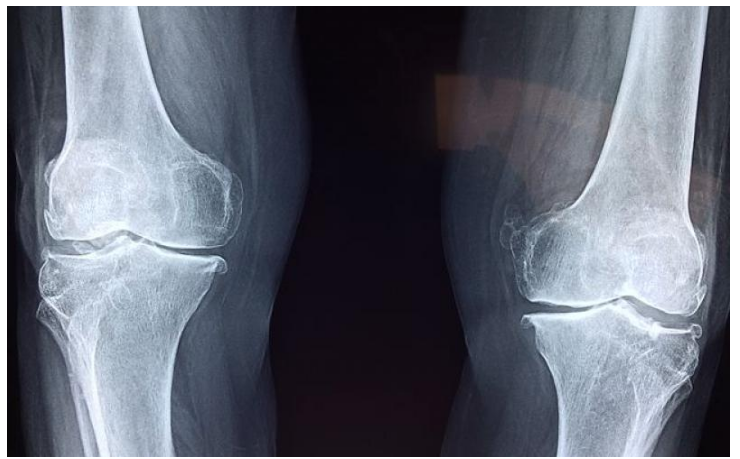

6. 用于骨科修复的生物制剂

骨科手术后,身体可能需要数月至数年才能恢复。但生物制剂(细胞、血液成分、生长因子和其他天然物质)具有替代或利用人体自身力量并促进治愈的能力。这些制剂正在不断用于骨科护理领域,以加快患者病情的恢复。